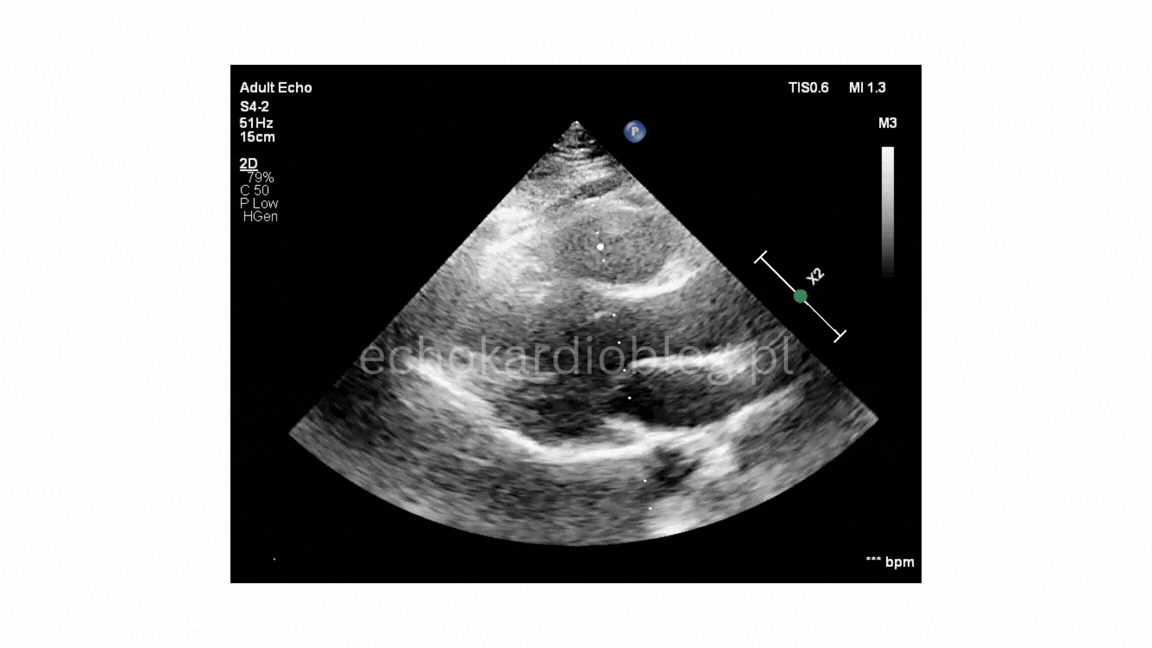

W trzecim – warunki obrazowania są trudne i nawet przy podejrzeniu BAV potwierdzenie diagnozy może być niepewne.

In the third, imaging conditions are very challenging, and even if BAV is suspected, confirmation may be uncertain.